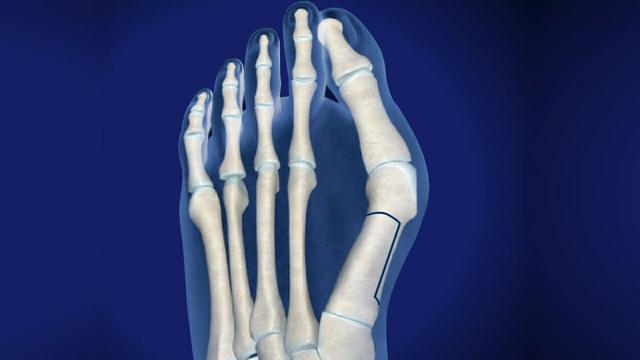

拇趾或第一趾,在脚的中远部。它由第一跖骨(有两个籽骨的关节)、第一近节指骨和第一远节指骨组成。所以拇趾不像其他脚趾有一块额外的骨头叫做中间趾骨。

第一个脚趾有三个滑膜关节。第一个关节是跖跗关节位于内侧楔形骨和第一跖骨之间,不允许大幅运动。第二个关节是跖趾关节,连接第一跖骨和第一近端趾骨。该关节允许第一个脚趾的弯曲和伸展,以及向第二个脚趾中心的小幅度的外展和内收。它同时被韧带加强(包括:跖趾侧副韧带和跖板)。最后一个关节是趾间,是第一趾两趾骨之间的连接。这个关节只允许屈曲和伸展,它也被韧带加强。

如前所述,有两块籽骨与第一块跖骨相连。这些籽骨保护附着在肌肉上的肌腱,但它们的主要功能是通过伸展杠杆帮助肌肉产生更多的力量。

其他结构:胫前肌、拇长伸肌、腓骨长伸肌、拇长屈肌、拇短伸肌、拇外展肌、拇短屈肌、拇内收肌、背内侧肌、跖腱膜。